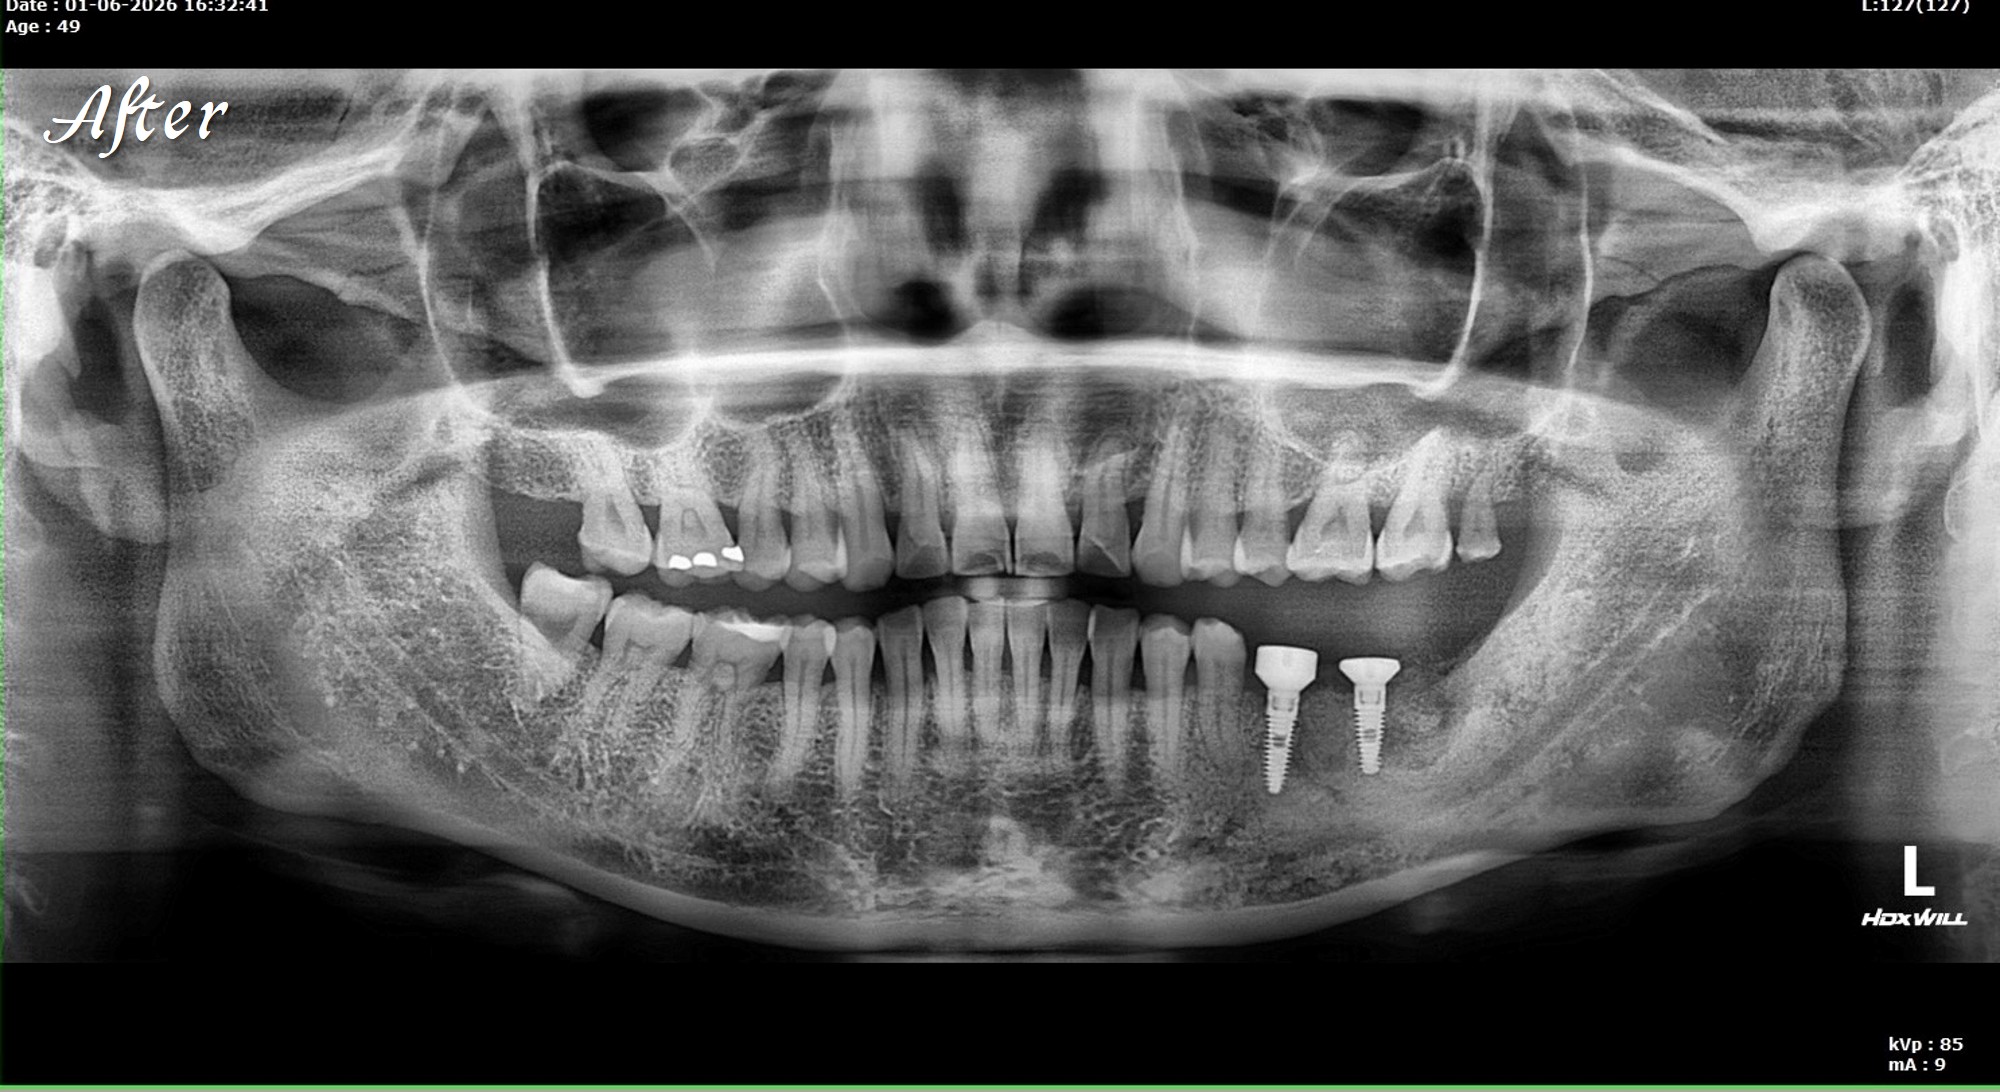

精奈創一鑽植牙系統團隊|3.5個月完成的植牙案例

一位初診新患者,陳博士評估後進行治療。

植牙後約3.5個月骨整合完成,骨頭穩定生長良好。

這樣的恢復速度,與Ezechbone的特性有關,

但最重要的是要有良好的primary stability。

接下來就是裝固定假牙。

對患者來說,療程清楚、恢復順利、生活品質不受影響;

對醫師來說,節奏穩定、結果可預期,不用提心吊膽。

治療變得簡單安心,身心靈也都被照顧了。